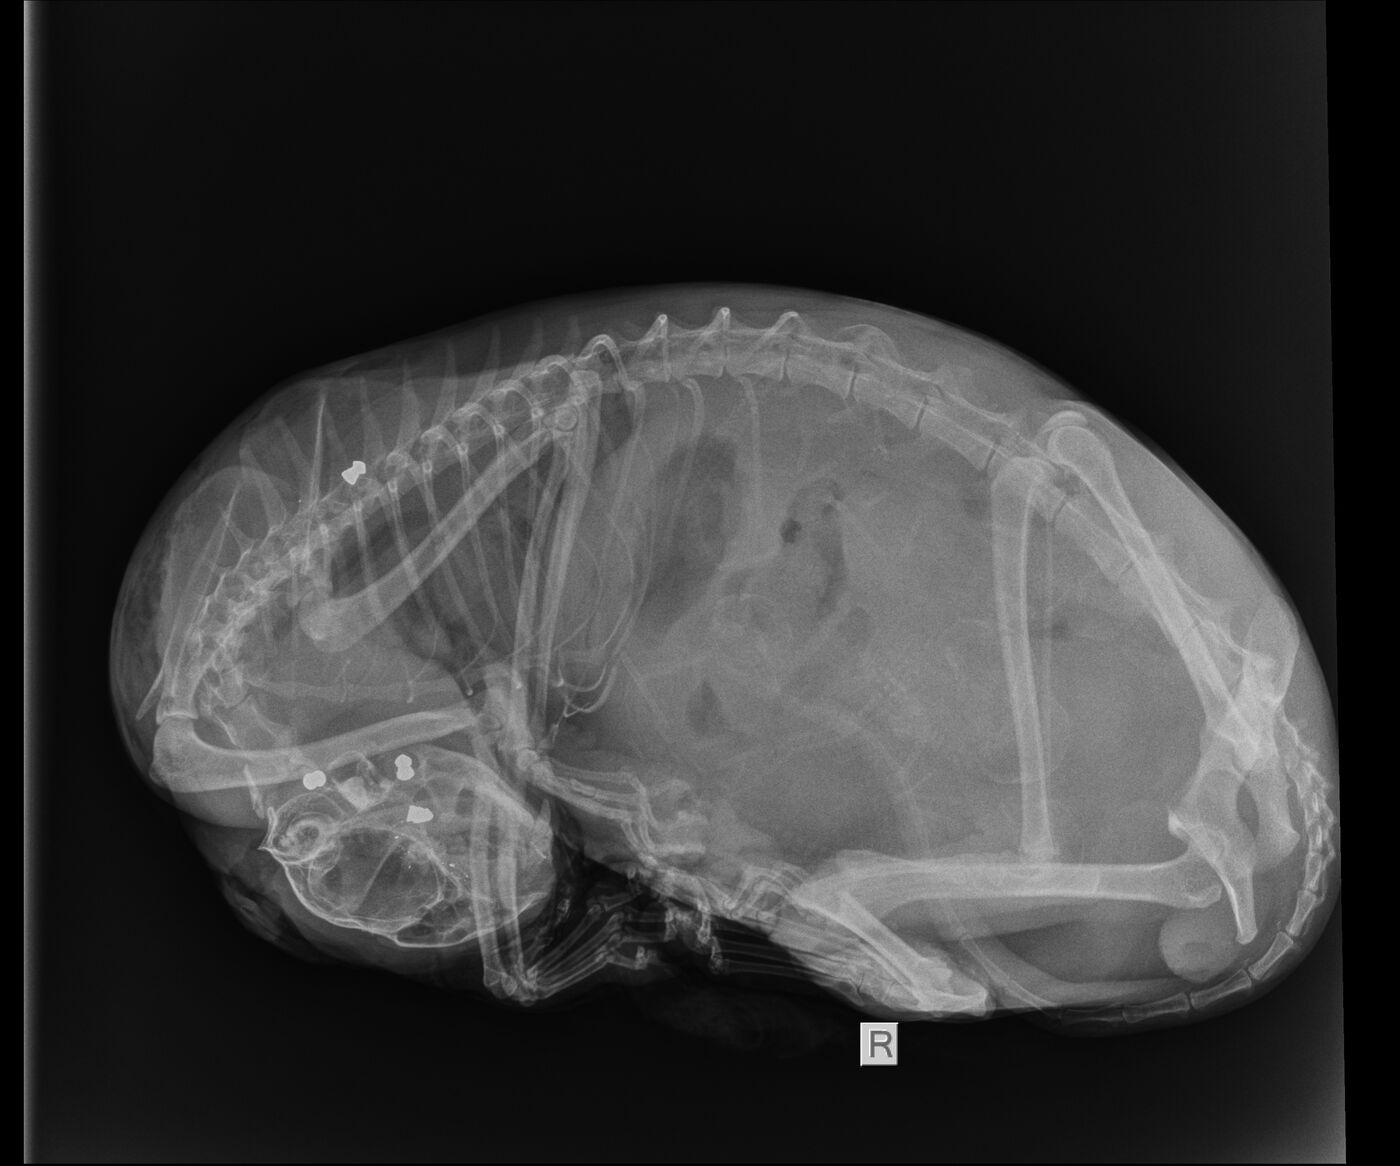

Unbekannte haben eine trächtige Katze offenbar mit einem Luftgewehr beschossen und so ihren Tod verursacht. Das Tier wurde am Mittwoch mit schweren Verletzungen im Tierheim „Vielauer Wald“ abgegeben. Eine Frau hatte es am Straßenrand zwischen Hartmannsdorf und Dänkritz gefunden. Jede Behandlung brachte nichts. Die Katze und ihre sechs Jungen im Bauch verendeten einen Tag später.

Auf den Röntgenbildern wird deutlich, wie es dem Tier ergangen sein muss. „Drei Projektile steckten im Kopf der Katze. Das lässt den abartigen Schluss zu, dass sie fixiert gewesen sein muss und der Täter oder die Täterin dann auf sie geschossen hat“, sagte Tierheimchefin Claudia Ruf unserem Sender entsetzt. Ein viertes Projektil wurde in der Schulter der Katze gefunden.